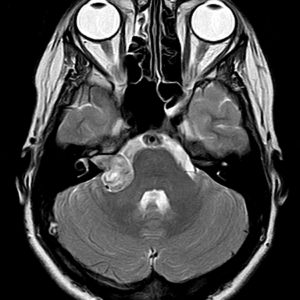

U dây VIII

Lượt xem: 132» 24-11-2018 -

U dây VIII

Lượt xem: 130» 24-11-2018 -

U dây VIII

Lượt xem: 153» 24-11-2018 -

U dây VIII

Lượt xem: 147» 24-11-2018 -

U dây VIII

Lượt xem: 117» 24-11-2018 -

U dây VIII

Lượt xem: 149» 24-11-2018 -

U dây VIII

Lượt xem: 143» 24-11-2018 -

U dây VIII

Lượt xem: 158» 24-11-2018